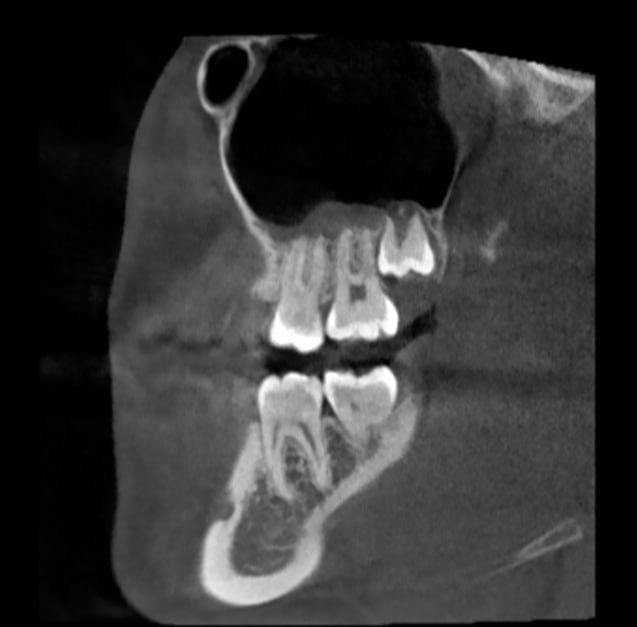

Здравствуйте, уже год беспокоит увеит и повышенная температура. Врач сказал искать причину увеита в воспалении в близлежащих органах. Проверила пазухи носа, лор не заметил патологий и перенаправил к стоматологу из-за отека на снимке над зубами. Подскажите, из-за чего может быть отек на снимке, если лор-патологии исключены? Что с зубами?

С зубами всё нормально (во всяком случае в том срезе КТ, который Вы предоставили), а при гипертрофии слизистой гайморовой пазухи, говорить об отсутствии патологии со стороны ЛОР-органов не приходится...